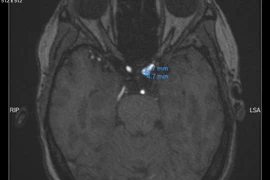

Bn Hậu Covid-19 tới khám tại bệnh viện Thanh Nhàn